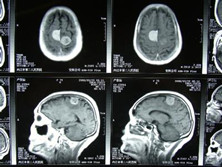

多发性脑膜瘤

头部MRI、头部CT